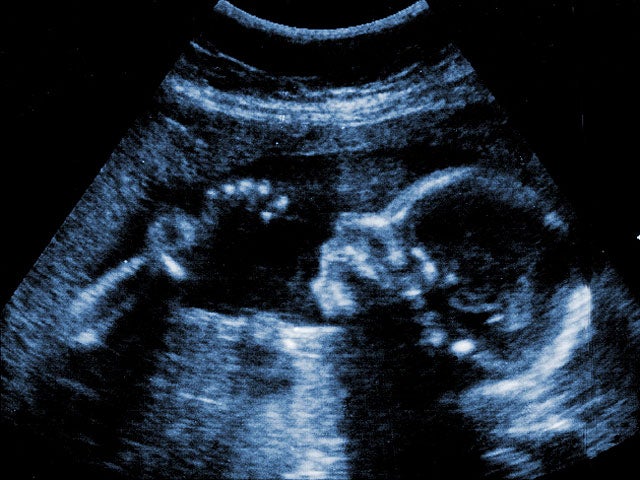

Republicans in the Texas House will demonstrate their newly-gained power today when they give the official approval of a bill that would require women to get a sonogram before having an abortion.

In response to the forceful objections raised by Democrats, Republican lawmakers pointed out that a woman may choose "not to receive the information" from the sonogram, the Associated Press reports. In other words, a woman would not be penalized for looking away from the image of the fetus, or wearing headphones to avoid hearing a heartbeat.

State Rep. Carol Alvarado, according to the Associated Press, carried an ultrasound wand onto the House floor on Wednesday and on Thursday, described in detail how the tool is used. "This is government intrusion at an all-time high," she said.